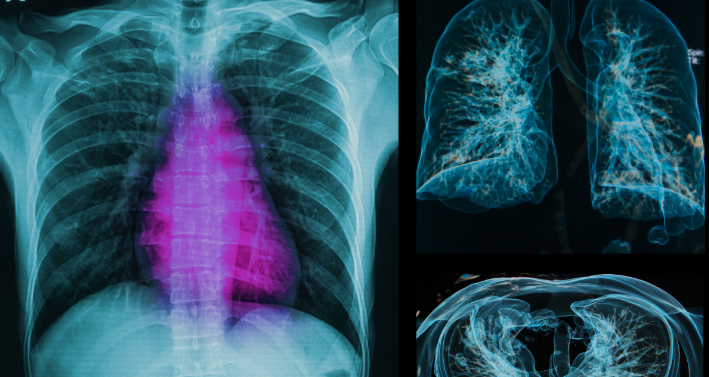

MRI